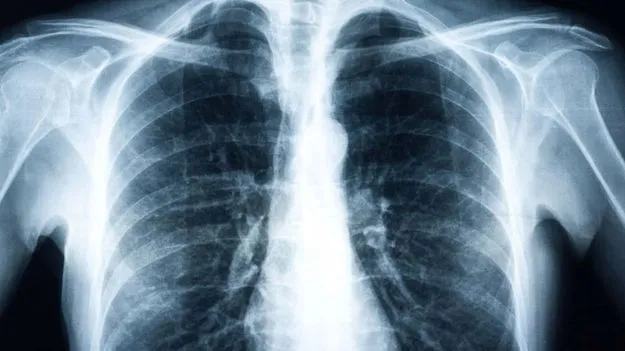

ఊపిరితిత్తుల ఎక్స్‌రేను పరిశీలించేందుకు ఉద్దేశించిన ఓ ఏఐ టూల్‌ చేసిన అద్భుతం చూసి ఆయన ఈ కామెంట్ చేశారు. కేవలం సెకెన్ల వ్యవధిలోనే ఏఐ టూల్ ఓ ఎక్స్‌రే ఫిల్మ్‌ను పరిశీలించి రోగం ఏంటో కనిపెట్టేసిందని అన్నారు. తాను గుర్తించని అంశాలను కూడా హైలైట్ చేసిందని చెప్పుకొచ్చారు. అంతిమంగా, పేషెంట్‌కు సరైన వైద్యం అంది కోలుకున్నారని కూడా తెలిపారు.

‘‘ఇలాగైతే నా జాబ్ పోయినట్టే, ఎక్స్ రే ఫిల్మ్‌ను చూసి రోగం ఏంటో చెప్పే నైపుణ్యాన్ని సాధించేందుకు నాకు 20 ఏళ్లు పట్టింది. కానీ ఇదే ఎక్స్ రే ఫిల్మ్‌ను ఏఐ టూల్ సెకెన్ల వ్యవధిలోనే అర్థం చేసుకుని రోగం ఏంటో చెప్పేసింది. ఇకపై ఎక్స్‌ రేలను నిపుణులు పరిశీలించాల్సిన అవసరం లేదు. ఏఐ సరిపోతుంది. ఇక నేను వెళ్లి మెక్‌డోనల్డ్స్ ఫాస్ట్ ఫుడ్ సెంటర్‌లో జాబ్ వెతుక్కుంటాను. నాకు అక్కడ జాబ్ దొరక్కపోదు’’ అంటూ సరదాగా కామెంట్ చేశారు.